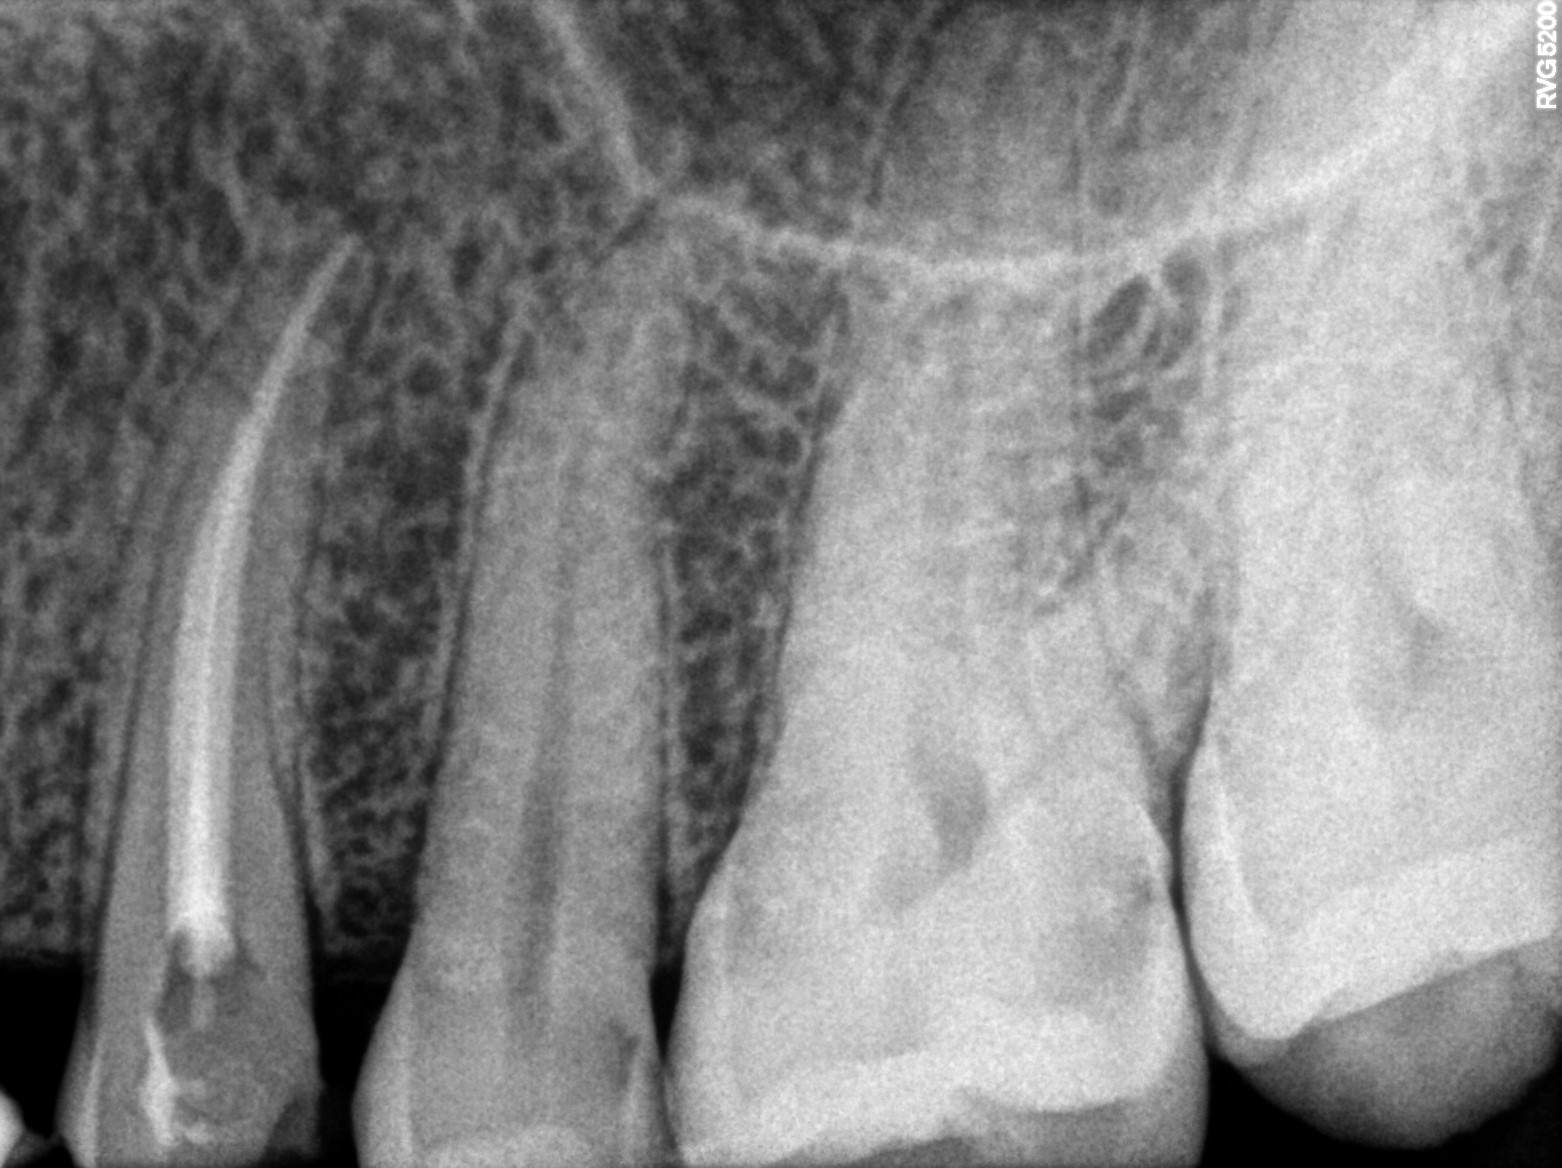

Dental Radiographs FHIR: DocumentReference · LOINC 24641-7

R56 (2).jpg

24641-7